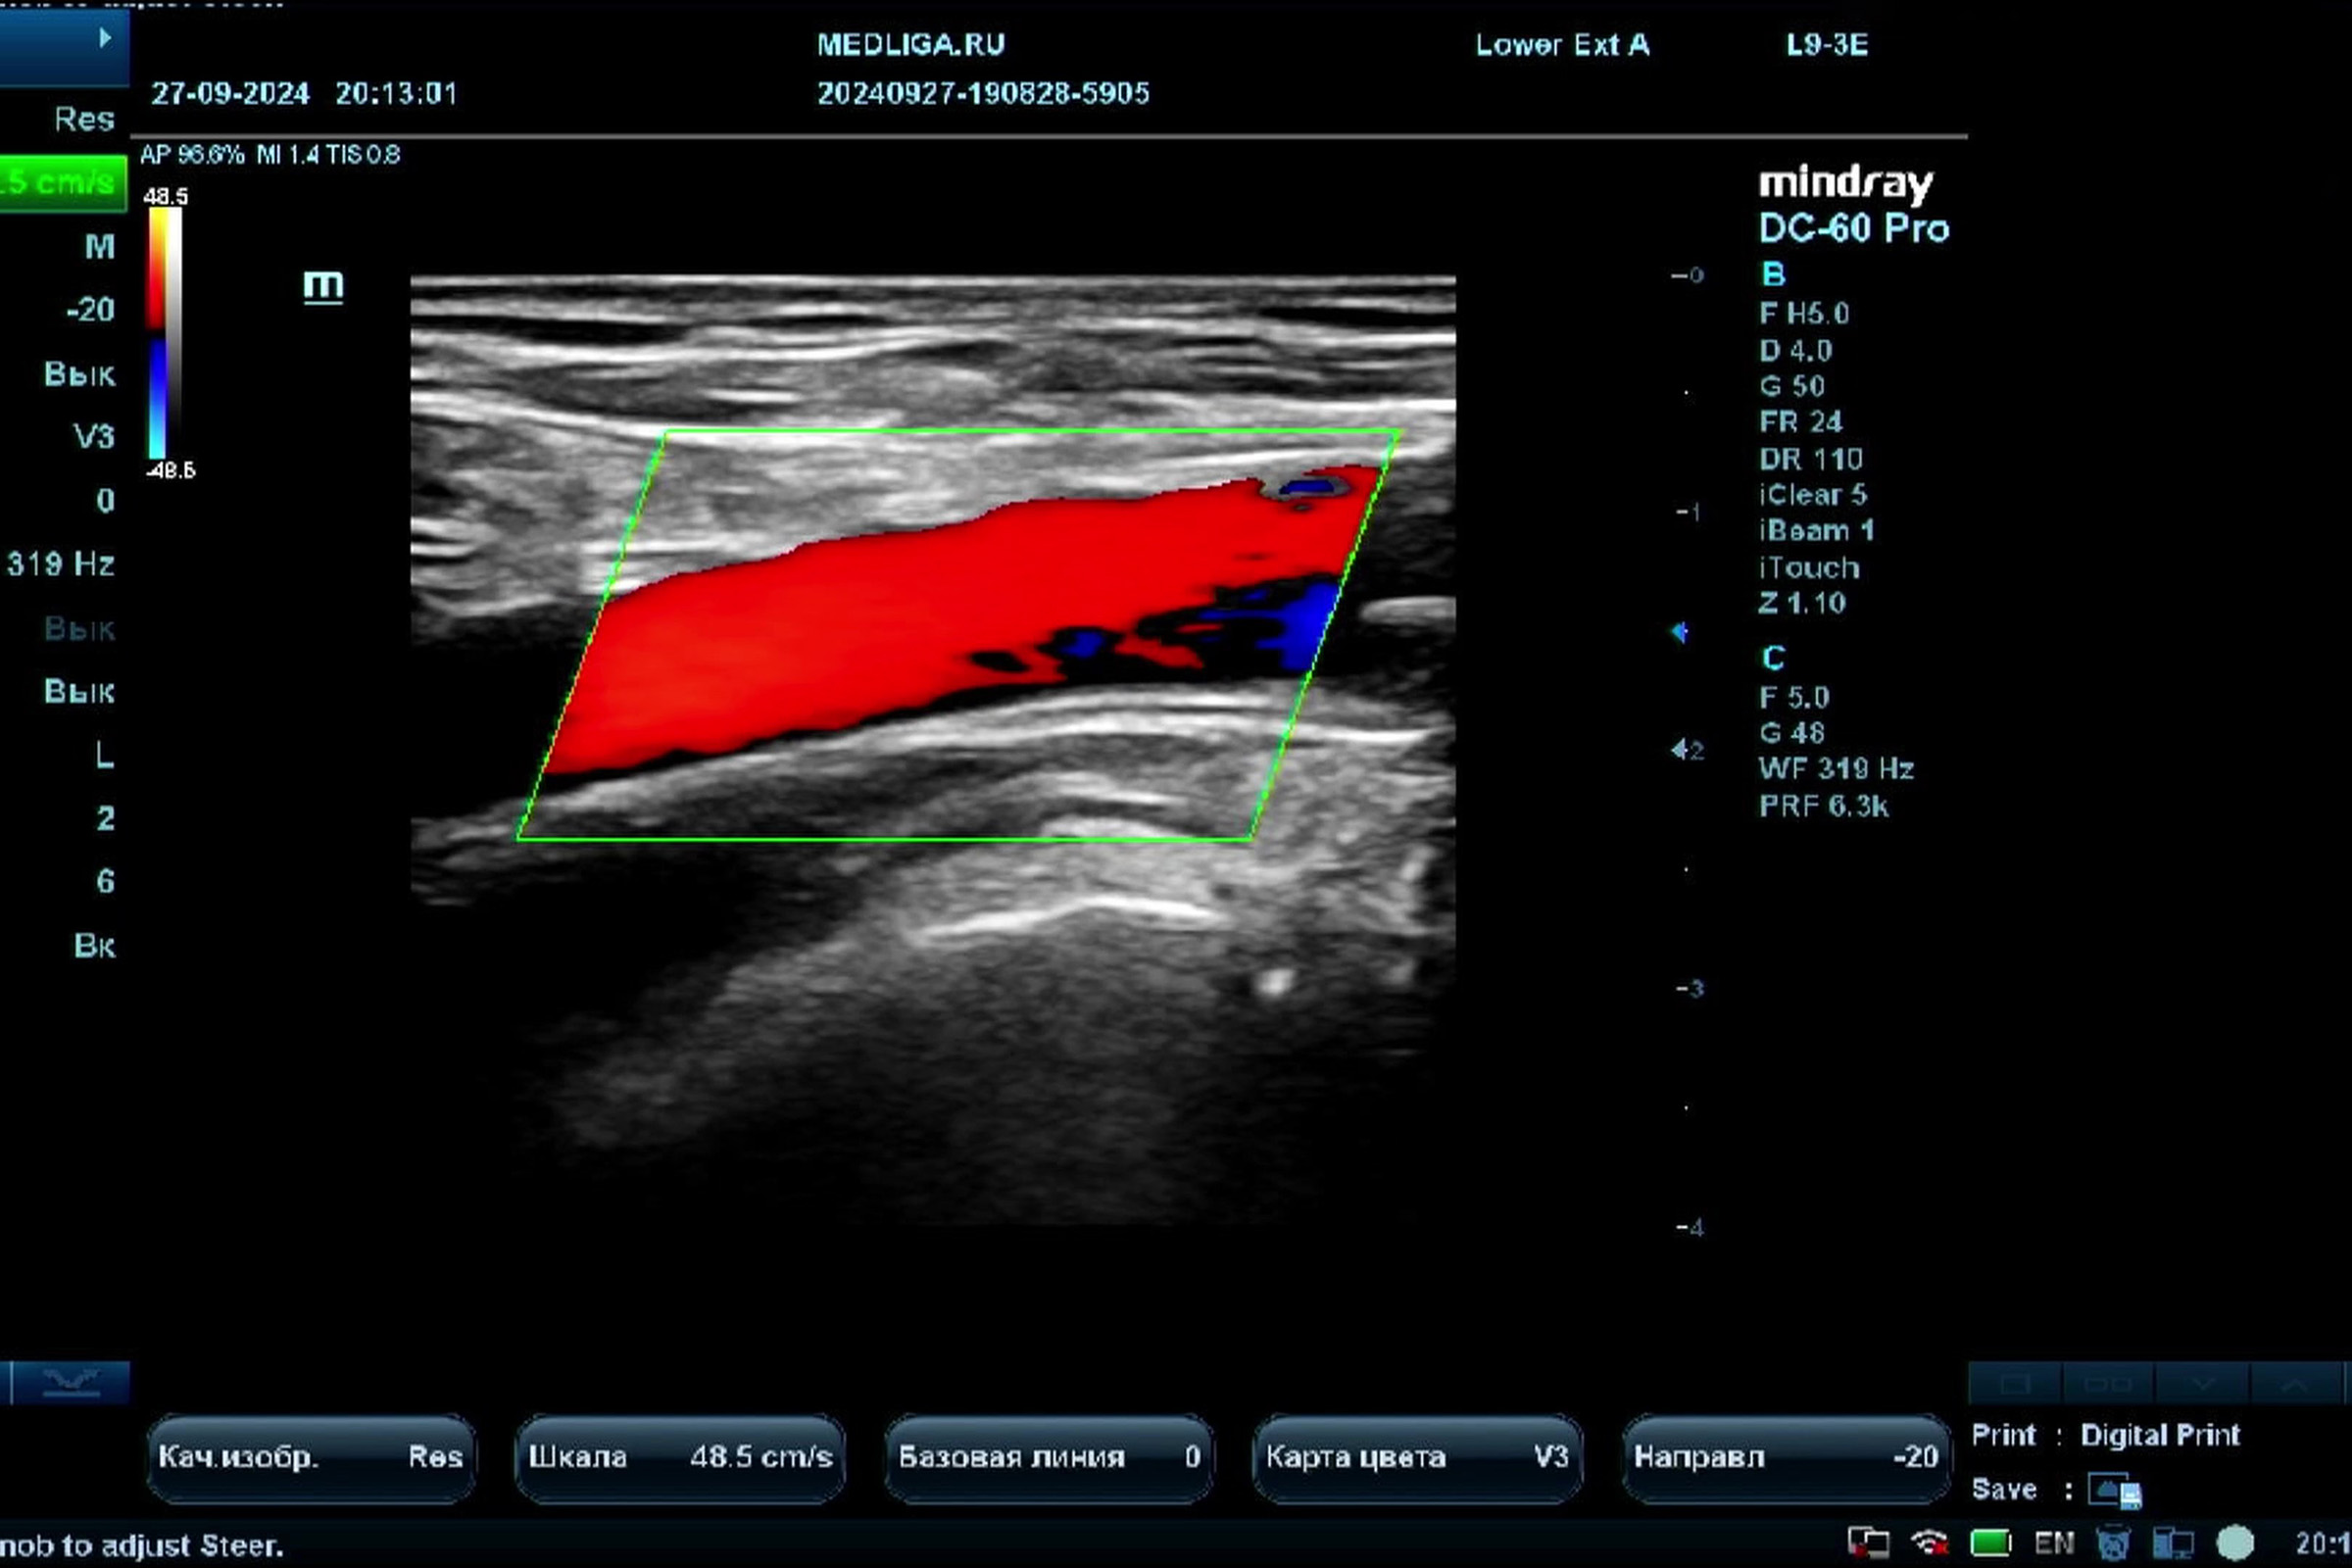

Видео узи артерий

Видео узи артерий 107 фото